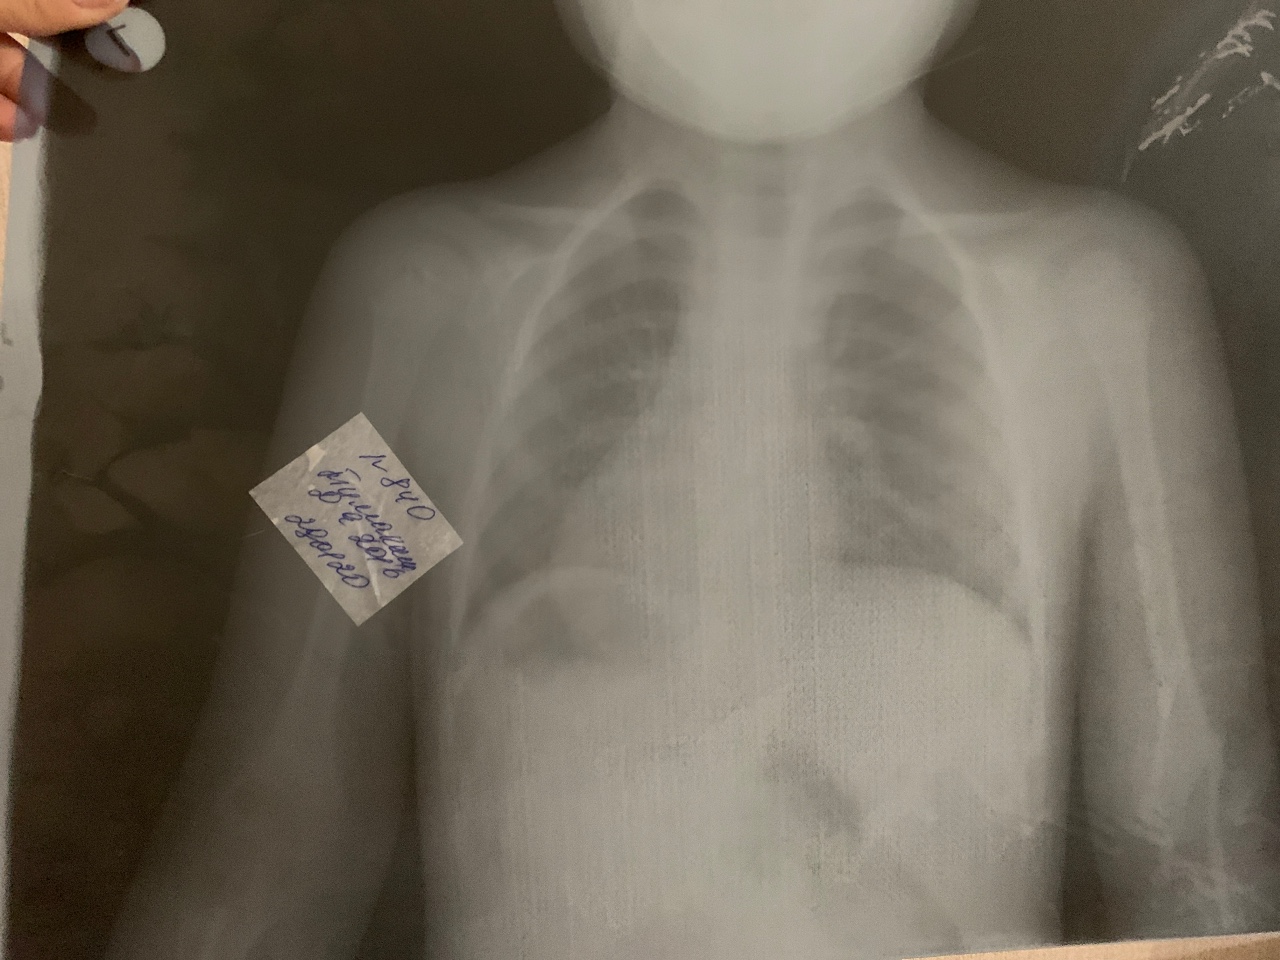

Снимок грудной клетки здорового ребенка: примеры и диагностика